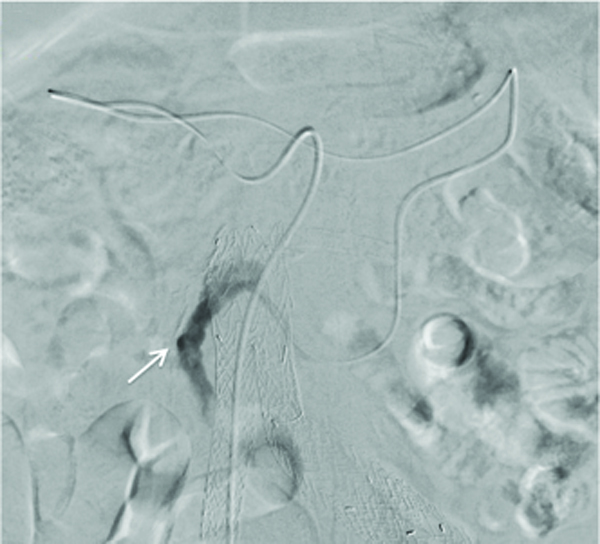

From www.researchgate.net

Coil embolization in a patient with type 2 endoleak. Download Coil Embolization Of Type Ii Endoleak  1) transarterial embolization of the feeding vessel accessed from the superior mesenteric or internal.  aneurysm sac coil embolization during evar for patients at risk for type ii endoleak is technically feasible, safe, and effective in.    — a type ii endoleak after endovascular aneurysm repair can be challenging to stop.    — frequently used strategies include: Embolization procedures for. Coil Embolization Of Type Ii Endoleak.